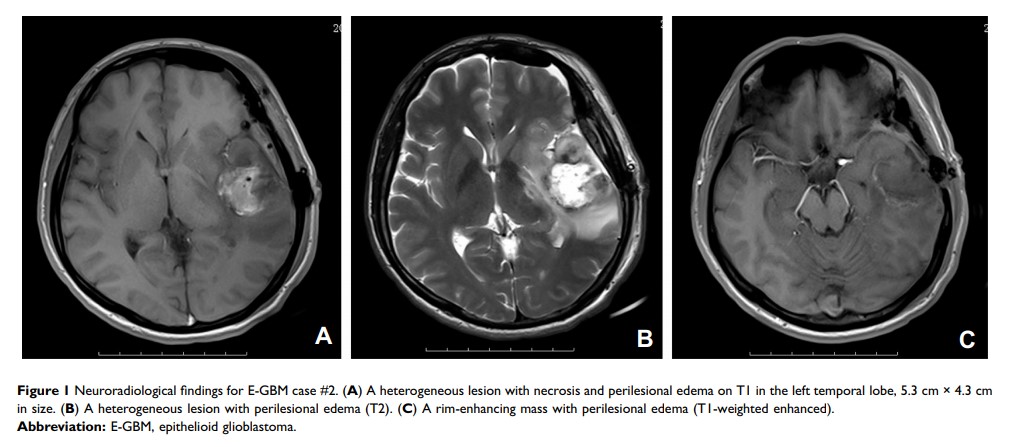

上皮样胶质母细胞瘤的临床病理、免疫组织化学和分子遗传学研究:15 例病例系列及文献综述